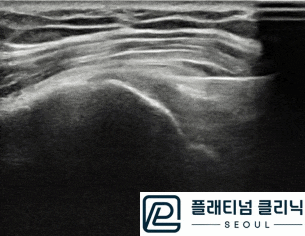

(플래티넘의원) 회전근개 질환 진단시 초음파 만으로도 충분히 진단이 가능합니다.

안녕하세요. 정형외과 전문의 이동규원장입니다. 환자분들이 어깨 질환이 있으면 꼭 MRI 를 찍어야 하냐...